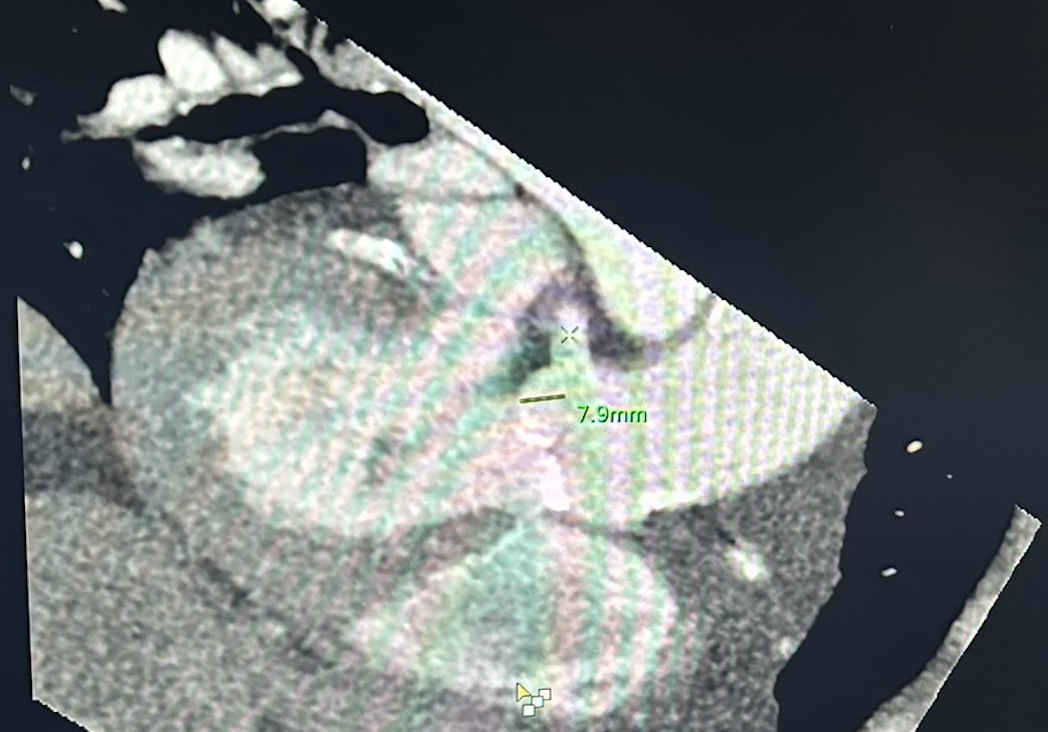

• RCA + Aortic valve in same plane with measurement included (left image)

• Left main + Aortic valve in same plane with measurement included (right image)